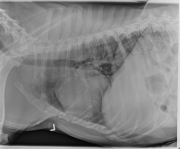

This week’s case is an 11-year-old Pit Bull Terrier. This dog is lame on the left pelvic limb. What are your findings?

Thorax: The cardiovascular structures are normal in size and shape. The thorax is hypoinflated. No pulmonary nodules are visible. There is a small convex opacity dorsal to the second sternebra. The mediastinum and pleural space are normal. There is mild osteophyte formation in the shoulder joints.